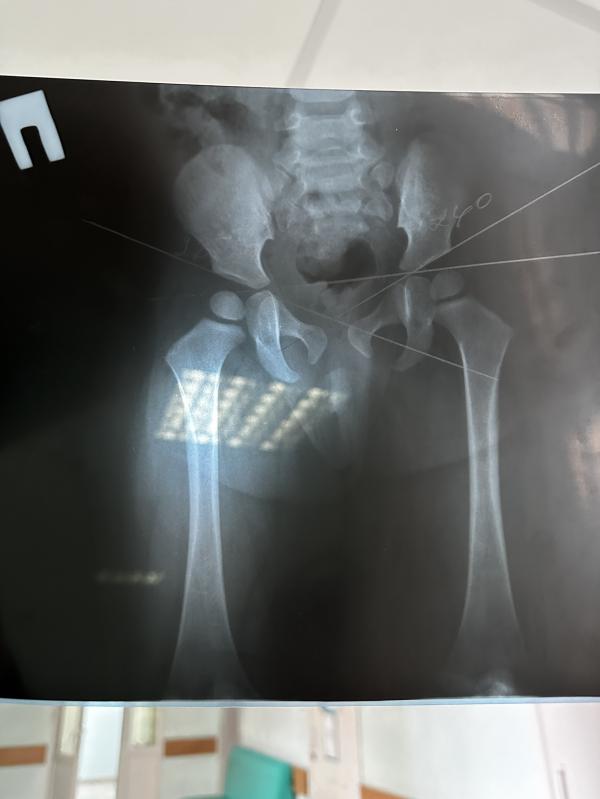

Нам 1.2 обнаружели дисплазию тазобедренных суставов. У кого было? Как исправляли? Это серьёзно?

Серьёзно, нужно к ортопеду, у вас ещё малышка совсем, хорошо вовремя заметили, а мы в 12 лет квоту ждём на операцию по исправлению🥲

Только у нас не врождённое, а приобретенное потому что ребёнок не ходит